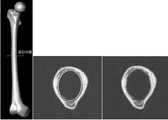

도 63 성별간의 IM 관 형상 차이.

Fig. 63 Difference in the shape of the IM tube between genders.